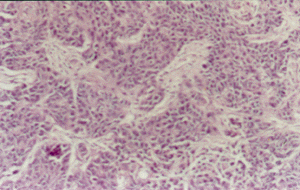

最后,将HNE1、#3-2和#4-2三种细胞系分别注入裸鼠皮下以观察这三种细胞的成瘤性。接种HNE1和#3-2细胞的裸鼠在接种后6天就出现了肿瘤,而接种了#4-2细胞的裸鼠在接种后11天才有肿瘤生成,说明#4-2细胞系致瘤的潜伏期比HNE1和#3-2细胞系延长。3周以后取出肿瘤进行病理诊断均为低分化鳞癌(图4),免疫组化和原位杂交都显示#4-2来源的裸鼠肿瘤组织中p16基因的表达明显强于HNE1和#3-2来源的裸鼠肿瘤组织(图5,6)。但三种细胞系所形成的肿瘤的重量没有明显的差别。

图4 鼻咽癌转染细胞系异体称植瘤的HE染色(×200)